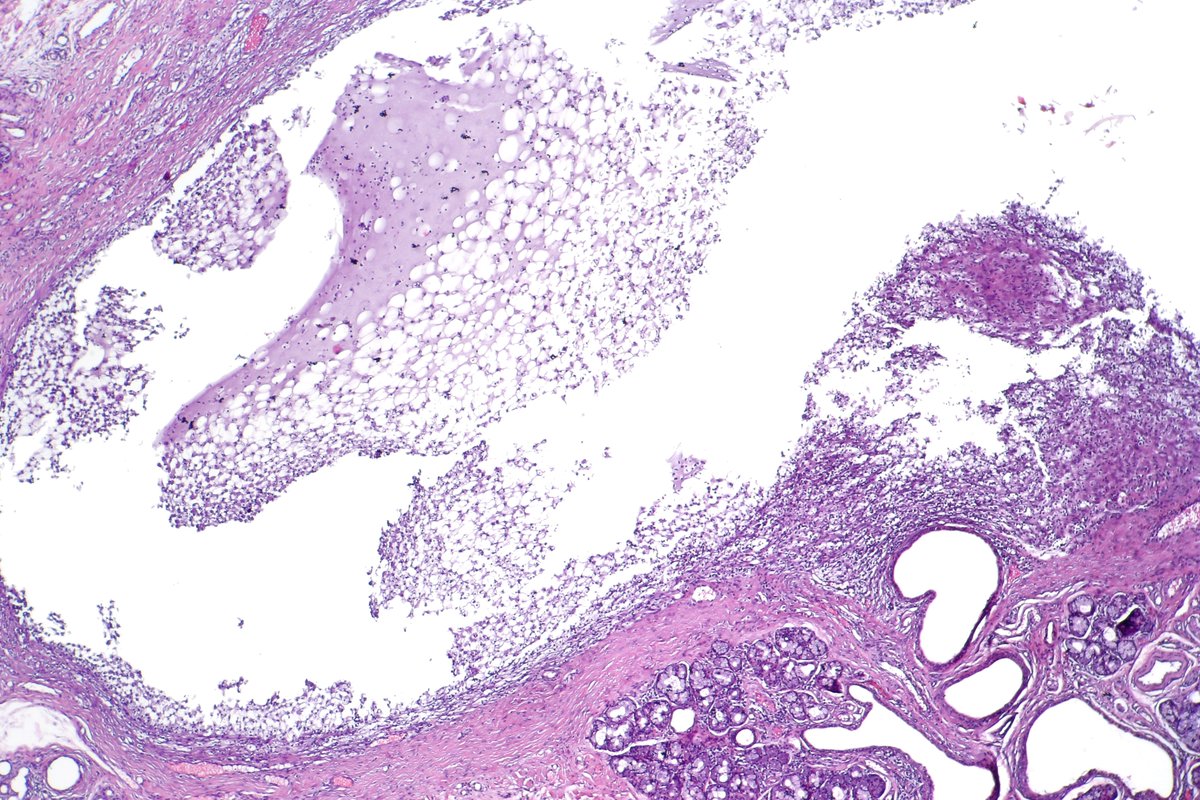

Atypical carcinoid of the lung exhibiting endobronchial growth, increased mitotic activity was seen (2-10 per 10 HPF). #pathology #PulmPath